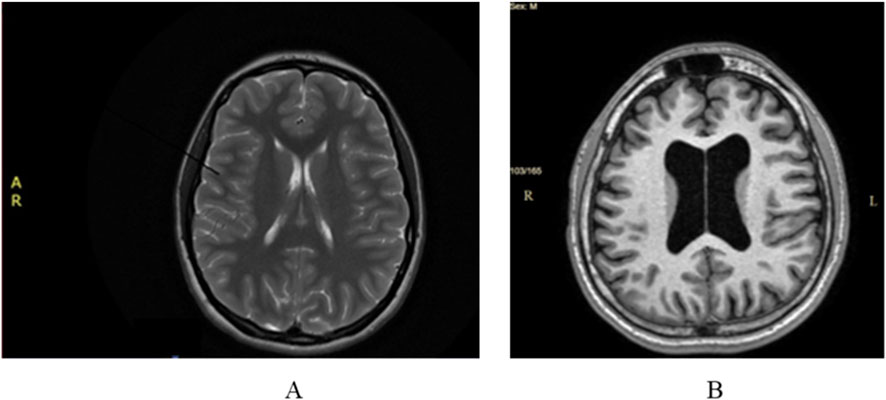

Cerebral magnetic resonance imaging (MRI) did not show any pathological modifications apart from 6 mm of fluid accumulation at the medial wall of the right maxillary sinus (Figure 1A).

Figure 1. (A) Case 1 normal cerebral MRI; (B) Case 2. Cerebral MRI: ventriculomegaly and global cerebral atrophy.

Cerebral MRI showed ventriculomegaly without neurosurgical indication and global cerebral atrophy (Figure 1B). Those imaging modifications were not considered to be significant in relationship with the extrapyramidal manifestations.